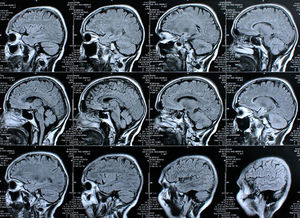

Gehirn-Screen: Rolle von Östrogen genau untersucht (Foto: pixelio.de, Rike) |